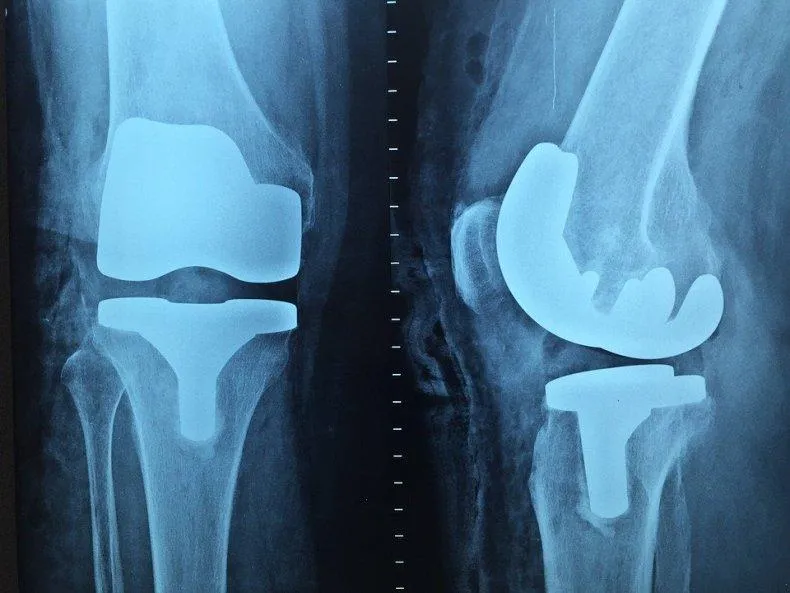

КТ проводят и после операций, особенно при внедрении металлических протезов, шунтов или кардиостимуляторов

Наиболее старый и привычный метод визуализации человеческого тела. Применяют рентген повсеместно, от хирургии до стоматологии. Метод прост и понятен: человека облучают особыми лучами, которые легко проходят сквозь мягкие ткани и задерживаются в твёрдых. Благодаря этому принципу, на фотоплёнку или датчик, расположенные на противоположной от источника лучей стороне, передаётся изображение, а в распоряжение врача попадает рентгенография или рентгеноскопия.

Главные плюсы такого обследования: быстрота и стоимость. Рентгеновскими аппаратами оснащены практически все больницы, процедура проходит быстро и стоит недорого.

Главные минусы: облучение и качество изображения. При проведении рентгенографии пациент облучается, а картинка получается двумерной. Врач с трудом может разглядеть внутренние органы по отдельности, поскольку их тени перекрывают друг друга. Также невозможно детально разглядеть хрящевую ткань и мозг. Хрящи практически не задерживает лучи, мозг надёжно закрыт черепной коробкой. Для их исследования рентгенография не подойдёт.

Наиболее эффективно будет проводить рентгенографию при повреждениях костей, суставов и зубов.